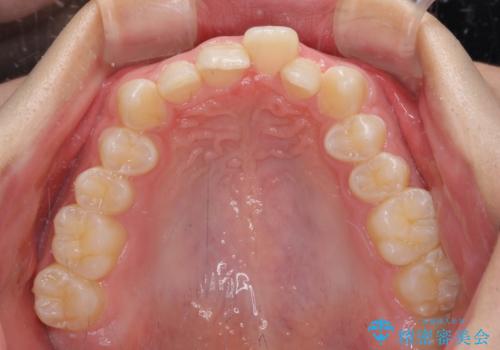

下顎前歯が全て隠れてしまうほどの深い咬合で、左右の奥歯は1歯対1歯で咬み合う状態でした。

前方に移動している上顎臼歯を補助装置にて遠心移動させることで1歯対2歯の臼歯咬合を目指し、同時に深い咬合を改善していくこととしました。